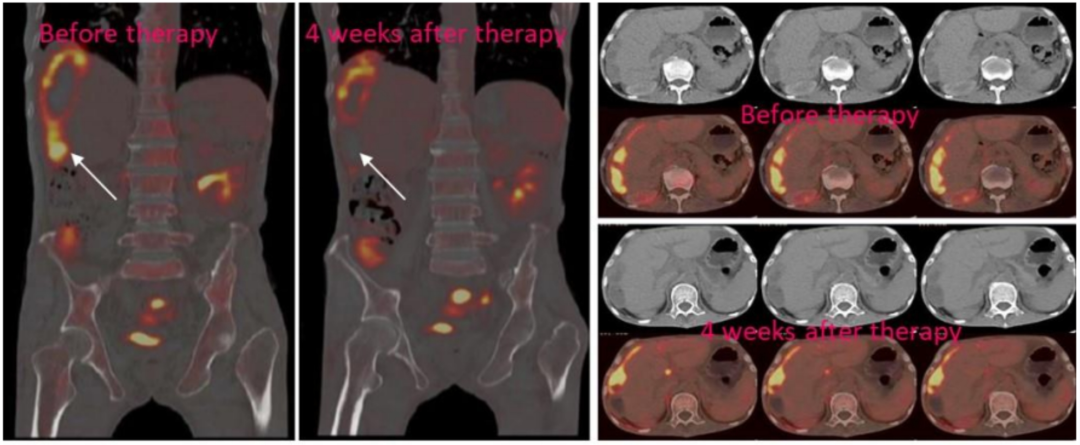

在该研究中,共入组3例转移性结直肠癌患者,通过局部输注的方式,给予NKG2DpCAR-NK细胞治疗。前两例患者经腹腔输注低剂量CAR-NK细胞后,可观察到腹水生成量减慢,且腹水样本中肿瘤细胞数量急剧减少。第3例患者发生了肝脏转移,采用腹腔内灌注+超声引导下瘤内经皮注射方式,给予CAR-NK细胞治疗后,多普勒超声可见肝脏肿瘤快速缩小;正电子发射断层扫描(PET-CT)提示,治疗后的肝脏病灶为完全代谢反应,详见下图。此外,这3例患者在治疗过程中,均未出现3级或以上的不良事件。

图2 CAR-NK细胞治疗后,肝转移病灶PEC-CT对比图

综上,本研究结果初步提示,NKG2D mRNA CAR-NK细胞治疗转移性结直肠癌的安全性和可行性,为难治性结直肠癌患者提供了一种新型的免疫治疗策略。